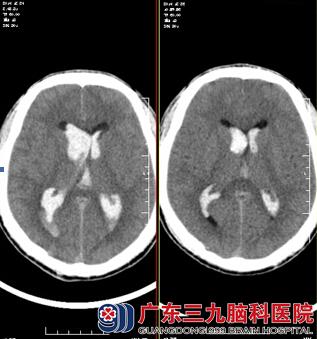

温先生正在上班时候突发头痛、呕吐,随后昏迷,只能发声不能睁眼。同事将温先生送到广东三九脑科医院就诊,头颅CTA示:胼胝体动静脉畸形;双侧脑室内出血;既往史:2009年曾因脑出血治疗,当时诊断为动静脉畸形,具体家属无法提供。

因病情紧急,由林涛主任主刀急诊全麻下为行“脑室外引流术”,术程顺利,术后予以预防感染、止血、脱水、支持、对症等综合治疗,2周后温先生意识逐渐好转。行全脑血管造影术,影像显示:左胼胝体区动静脉畸形;由于畸形较大,一次栓塞术难以处理,需分次进行。告知术中、术后相关风险后,家属表示理解并同意手术后行胼胝体体部动静脉畸形栓塞术,术程顺利,复查造影见动静脉畸形栓塞共约90%。术后复查头颅CT示:呈栓塞术后改变,未见新鲜出血。温先生康复出院。